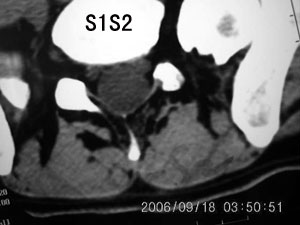

以下是引用守望可可西里在2006-9-18 21:29:00的发言:[br][br] 马尾肿瘤,密度较低,大部分似乎呈囊性变(看着很费眼),考虑室管膜瘤,建议mri。

以下是引用dyg在2006-9-18 22:27:00的发言:[br]正常脊髓.[br]分析:人的脊髓从枕大孔开始至腰1.2椎体为止,有2个生理膨大,分为颈膨大和腰膨大;该病人脊髓须然从腰段开始直至马尾似乎膨大,胆是与上段脊髓密度没有多大变化,所以我认为是正常膨大之延续;当然最好做ct增强或mri检查,排除肿瘤.

以下是引用飞虎在2006-9-18 20:18:00的发言:[br]部分椎管内密度不均且无ct值 故mri检查